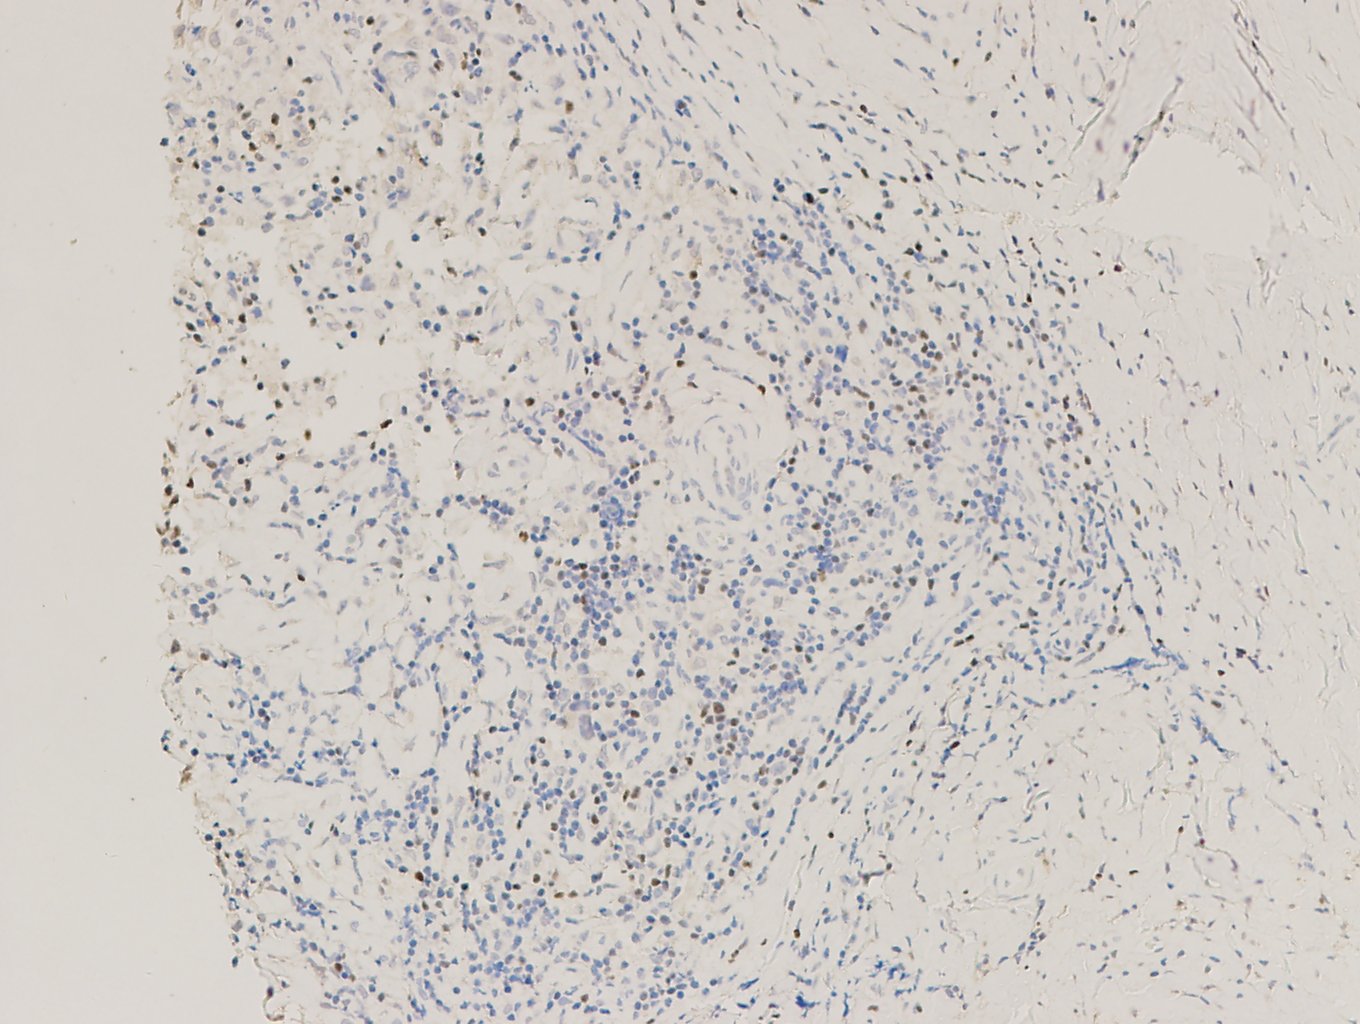

【新品單抗】FOXP3

| 克隆號 | 定位 | 陽性對照 | 修復(fù)條件 |

| EP340 | 細(xì)胞核 | 淋巴瘤 | 高PH熱修復(fù) |

霍奇金淋巴瘤,F(xiàn)OXP3染色,DAB顯色